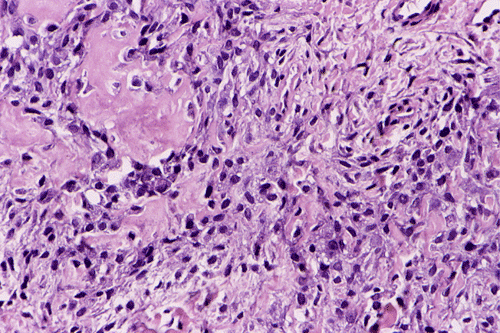

Pathology of the case:  An incisional biopsy yielded several small fragments of gritty, tan to translucent tissue. The histopathology varies in different parts of the tumor. In some areas, the lesion is composed predominantly of islands of neoplastic cartilage with focal osteoid formation and rimmed by spindle cells (Panel E). In other areas, densely packed spindle cells proliferation admixed with hypocellular fibrous tissues is present (Panel F). On high magnification, the spindle cells appear to be pleomorphic and hyperchromatic (Panel G). Mitotic figures are present but not numerous. No atypical mitoses are noted. Small foci of osteoid are best appreciated at higher magnification ("OS" in Panel G). It appears that this tumor has arisen from the medullary cavity and is best classified as a central osteosarcoma.

Osteosarcoma is a malignant tumor characterized by direct formation of bone or osteoid by the proliferating neoplastic cell. Other than sharing this characteristic, osteosarcoma is one of the most heterogeneous tumor from the histopathologic perspective.  The histologic features vary from different areas of the same tumor and among different tumors. In general, several major patterns are recognized: osteoblastic, chondroblastic, fibroblastic, giant-cell rich, small cell, telangiectatic,  and others. The amount of osteoid and ossified tissue can vary tremendously and it is not uncommon that it can only be found after careful search. The osteoid can form well-defined structures that mimic trabecular bone or as irregular deposits. The current trend is to classify osteosarcomas into low- and high-grade tumors. It is the histologic grade rather than tissue pattern that has greatest bearing on prognosis.

Similar to osteosarcomas arising from the flat bones and ribs (e.g., osteosarcomas of the pelvic bones), about 30% of the osteosarcomas of the jaws are chondroblastic type and contain a substantial amount of cartilage. Lobules of neoplastic cartilage may dominate the histologic picture in some cases and osteoid production by the neoplastic cells may occur only focally.  The cartilaginous differentiation can be heterogeneous and represent all stages of cartilaginous matrix formation. Stigmata of malignancies including nuclear pleomorphism, mitosis, atypical mitotic figures, and necrosis can all be seen in osteosarcomas.